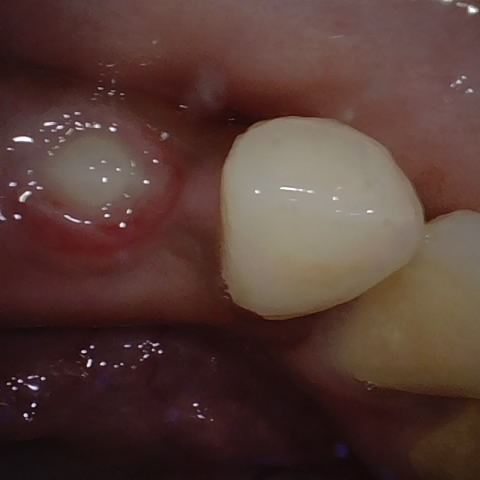

Annotated as "Good"